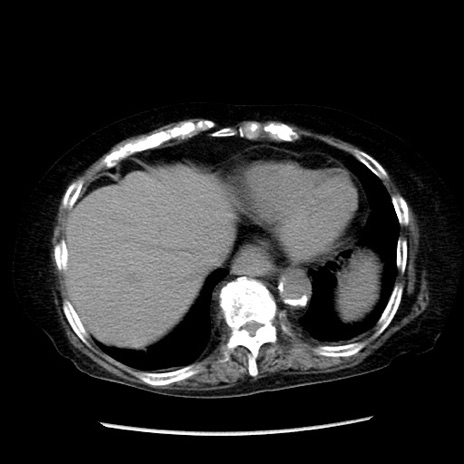

症例14(横断像)

【症例】 90歳代女性

【主訴】 腹痛・嘔吐

【現病歴】今朝から左側腹部痛を認めた。 経過観察していたが、嘔吐を認めたため来院。

【既往歴】 子宮癌術後

【身体所見】 意識清明、BP 127/54mmHg、P 98bpm Sp02 95%(RA)、BT 35.8°C、腹部平坦・軟腸ぜん動音聴取良好、右下腹部圧痛(+) 反跳痛なし

【データ】WBC 9800、CRP 0.46